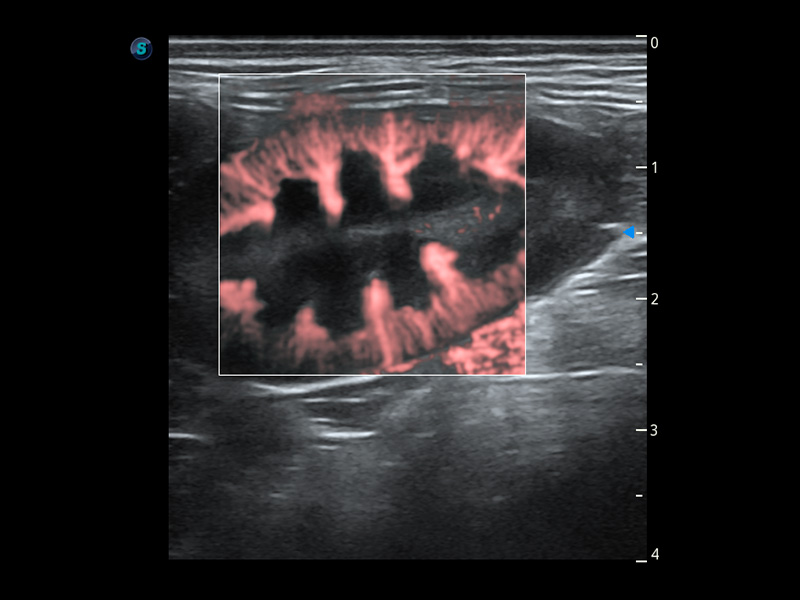

PDI 能量多普勒血流

提供高灵敏度和空间分辦率的血流图像,获得更加真实和丰富的诊断信息。

Bright Flow 立体血流成像

在传统二维血流成像的基础上,呈现血流的立体感,具有动感的生命力之美。精确区分不同血管的空间关系,提高了血流的视觉敏感性。

(犬)四腔心血流